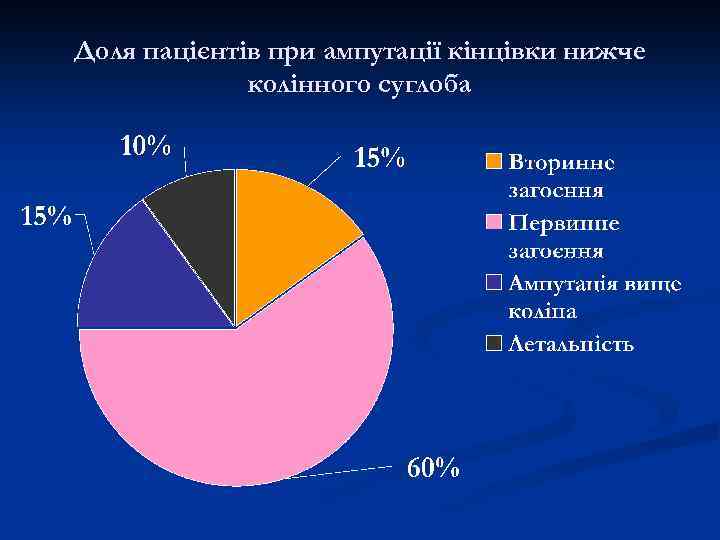

Доля пацієнтів при ампутації кінцівки нижче колінного суглоба

Доля пацієнтів при ампутації кінцівки нижче колінного суглоба